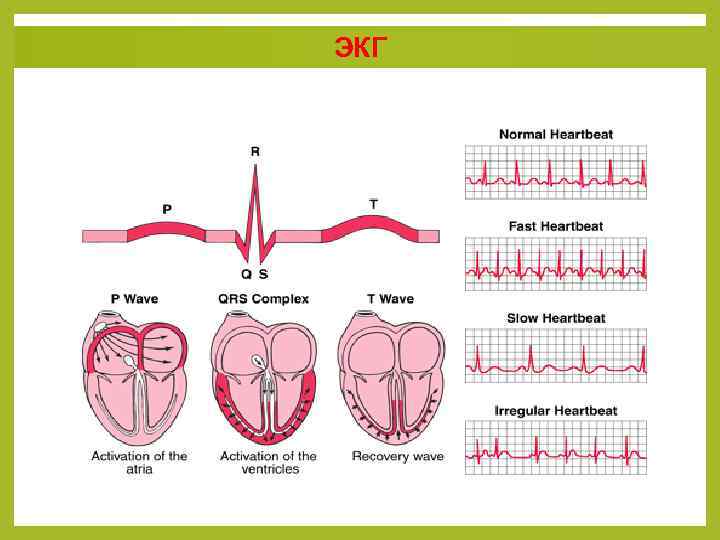

ЭКГ